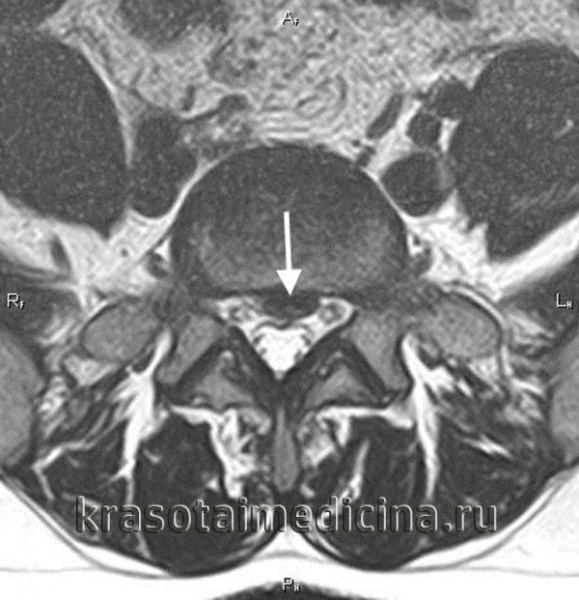

МРТ ШОП. Грыжевые выпячивания дисков в с. С5-С6, С6-С7 кзади, с выраженным сужением позвоночного канала и сдавлением спинного мозга

МРТ шейного отдела позвоночника. Межпозвонковая грыжа в сегменте С5-С6, отслаивающая заднюю продольную связку